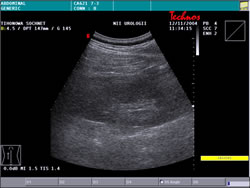

УЗИ: |

|